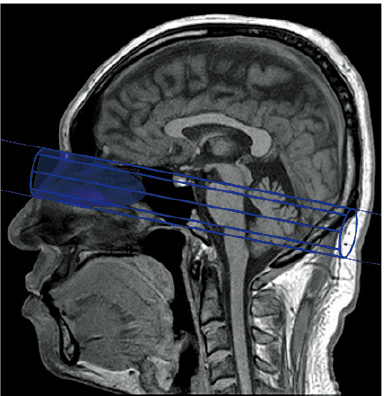

Pencil-beam type pre-saturation (BeamSat) pulses based on the application of local excitation are used in TOF imaging to selectively suppress some of the blood flow signals required for identification of the hemodynamics.

If imaging is conducted with BeamSat pulses specified for a target blood vessel, the flow signals of that vessel can be suppressed, and the dominant region can be identified. BeamSat pulses can be set to arbitrary positions and angles using a special GUI. The positions of BeamSat pulses can be set freely with respect to a target vessel.

High-precision control of pre-saturation pulses using the spiral-type two dimensional excitation method

Beam-form pre-saturation pulse realized by a high system performance

In the BeamSat display, the continuous line represents a nearer part and the broken line a part farther than the scanogram; the hatched part is a cross-section between a BeamSat and a scanogram.

SAG cross-section: Position contacting nasal root/sella turcica

AX cross-section: Position contacting pyramid/clivus